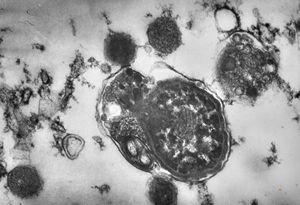

F,50y. | progressive multifocal leukoencephalopathy- viral particles in a glial cell

F,50y. | progressive multifocal leukoencephalopathy- viral particles in a glial cell

F,50y. | progressive multifocal leukoencephalopathy- viral particles in a glial cell